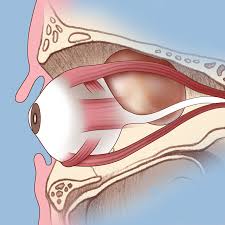

قیمت: 78٬750 تومان - دسته بندی فایل: علوم پزشکیپاورپوینت آناتومی orbit

orbit کره چشم در یک ساختمان استخوانی به نام اوربیت قرار گرفته حفره کاسه چشم (اوربیت) بصورت یک هرم چهار ضلعی است دیواره های داخلی اربیت در طرف راست و چپ موازی هستند و توسط بینی از هم جدا می شوند